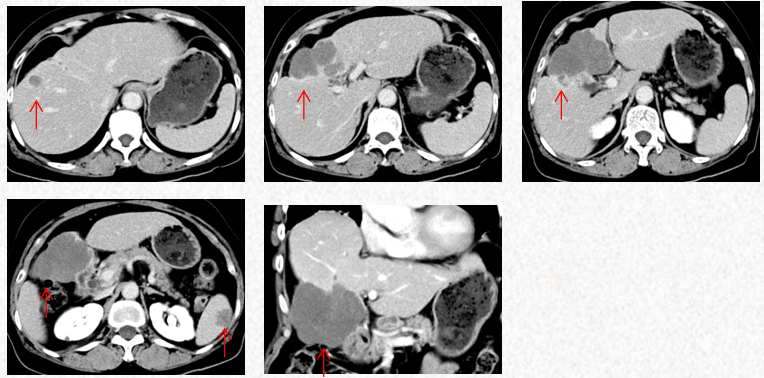

2023-3-19复查胸腹CT图片,最佳疗效评估为PR。

2023-3-19胸腹CT:肝肿物最大横截面积91*60mm,脾脏转移瘤(19*12mm)